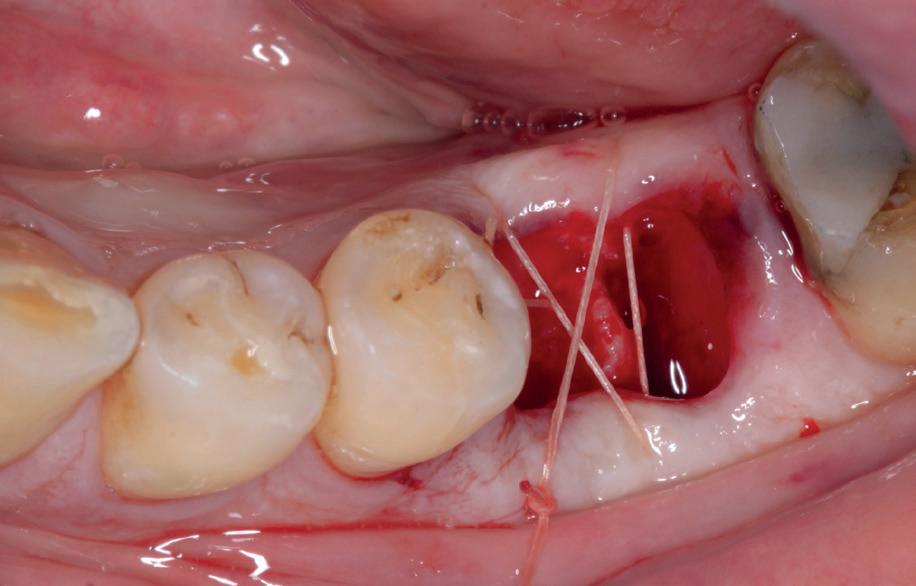

De implantaatplaatsing en de beslissende fout (afbeelding 1-13)

De extractie verliep voorspoedig, waarbij ik zoals al-

primaire stabiliteit van 60 Ncm.

11. Röntgenfoto ter controle van de plaatsing en de angulaire. Dit bone-level implantaat werd 4 mm onder de weke delen geplaatst.

12. Direct post-op. Een direct geplaatste tijdelijke kroon. Vastgezet met een torque van 20 Ncm en gehecht met prolene 5/0.

tijd probeerde de buccale botlamel intact te houden. Dit is cruciaal voor latere botbehoud en implantaatplaatsing. Na curettage en spoelen van de alveole beoordeelde ik de situatie opnieuw: de botcondities leken gunstig voor een immediaat implantaat.

Hier begon echter de cruciale fout in mijn klinisch besluitvormingsproces. In mijn streven naar maximale primaire stabiliteit - wetende dat immediaat belasten enkel mogelijk is bij hoge stabiliteit -on-

13. Röntgenfoto ter controle van de pasvorm van de direct geplaatste tijdelijke kroon.